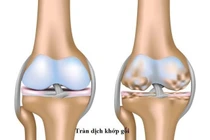

(khoahocdoisong.vn) - Thoái hóa khớp gối là quá trình lão hóa của tổ chức sụn khớp, đầu xương và các tổ chức phần mềm quanh khớp, được xếp vào chứng hạc tất phong trong Đông y. Là một quá trình tất yếu ở người có tuổi nhưng gần đây có xu hướng trẻ hóa ở người trung niên và người trẻ. Hiện y khoa đã có rất nhiều phương pháp trị liệu, bài viết này xin giới thiệu phương pháp vận động, xoa bóp bấm huyệt.

Viêm khớp gối là tình trạng phần xương sụn trơn bị mòn đi, khi đó, các khớp xương sẽ cọ xát vào nhau chặt hơn, ma sát nhiều, việc hấp thụ các chấn động ở sụn khớp giảm đi, gây đau và vận động khó khăn.

(khoahocdoisong.vn) - Người có tuổi xương khớp thường thoái hóa. Cứng khớp buổi sáng, ngay khi vừa thức giấc rất dễ xảy ra. Dấu hiệu này có thể kéo dài từ 30 phút và phải mất một thời gian dài vận động mới có thể mềm ra. Thêm vào đó, khi di chuyển, khớp phát ra tiếng động, nghe như tiếng lạo xạo hoặc lắc rắc.